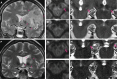

As a sequel of brain ischemia, selective neuronal loss (SNL)-as opposed to pannecrosis (i.e. infarction)-is attracting growing interest, particularly because it is now detectable in vivo. In acute stroke, SNL may affect the salvaged penumbra and hamper functional recovery following reperfusion. Rodent occlusion models can generate SNL predominantly in the striatum or cortex, showing that it can affect behavior for weeks despite normal magnetic resonance imaging. In humans, SNL in the salvaged penumbra has been documented in vivo mainly using positron emission tomography and (11)C-flumazenil, a neuronal tracer validated against immunohistochemistry in rodent stroke models. Cortical SNL has also been documented using this approach in chronic carotid disease in association with misery perfusion and behavioral deficits, suggesting that it can result from chronic or unstable hemodynamic compromise. Given these consequences, SNL may constitute a novel therapeutic target. Selective neuronal loss may also develop at sites remote from infarcts, representing secondary 'exofocal' phenomena akin to degeneration, potentially related to poststroke behavioral or mood impairments again amenable to therapy. Further work should aim to better characterize the time course, behavioral consequences-including the impact on neurological recovery and contribution to vascular cognitive impairment-association with possible causal processes such as microglial activation, and preventability of SNL.